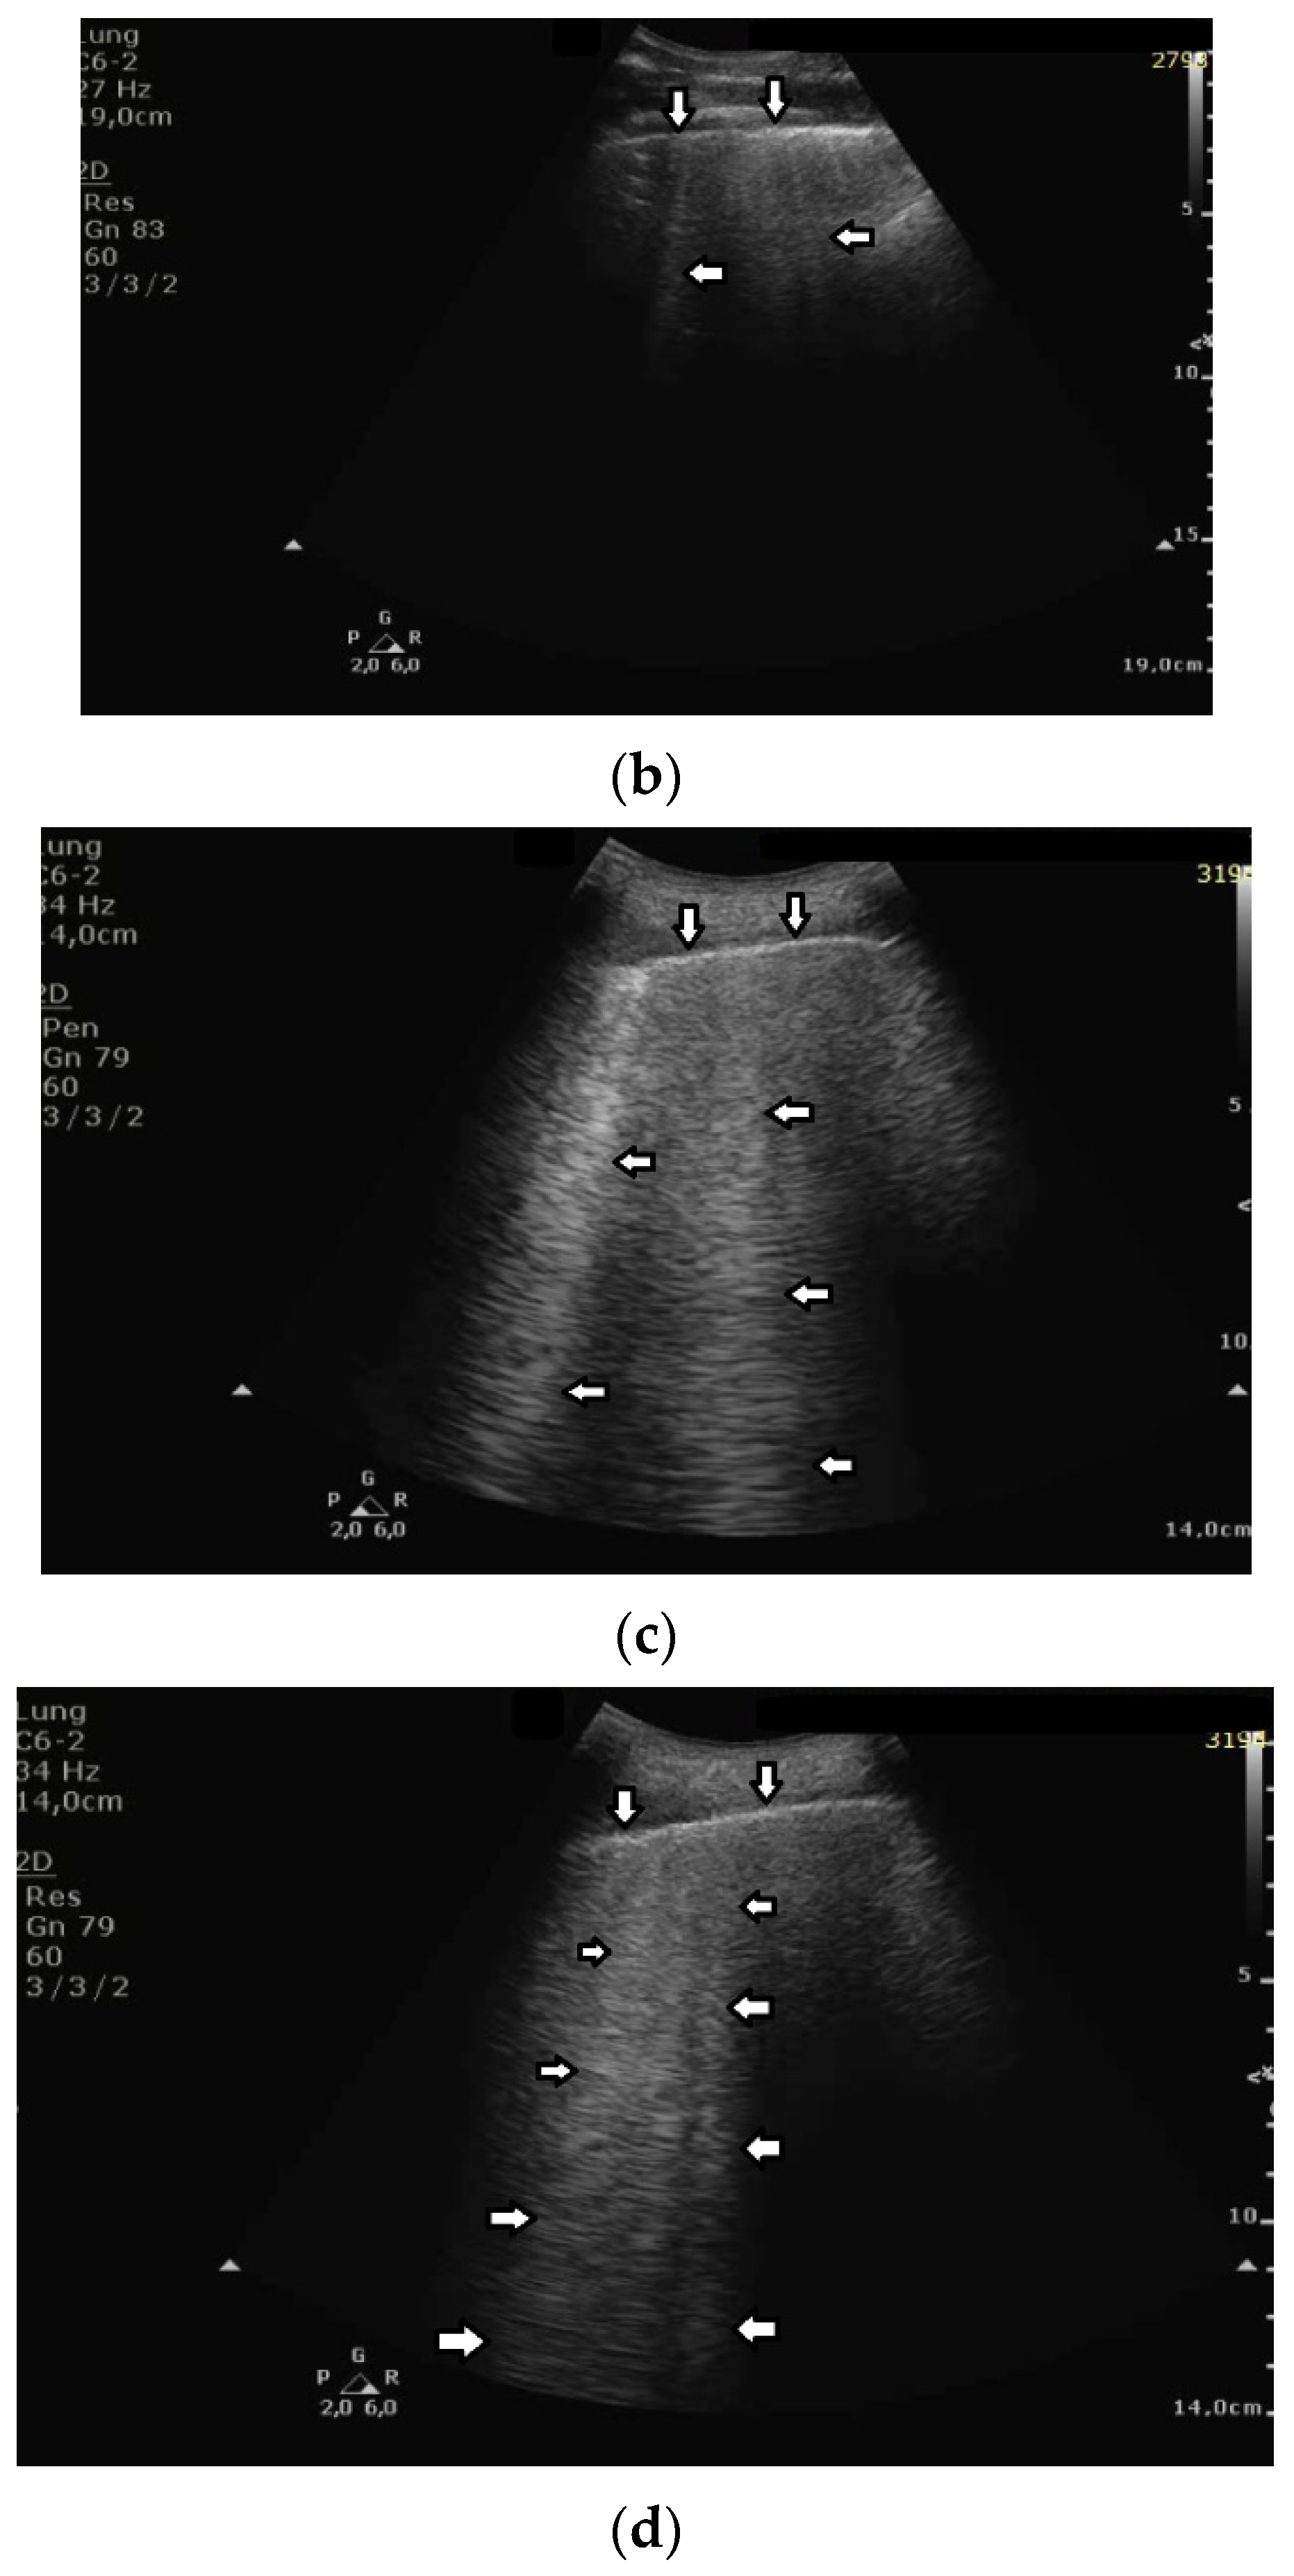

While monitoring the interstitial and alveolar involvement, we observe more and more confluent B lines which can evolve in a so-called white lung artifact which, in turn, can subsequently change to consolidation (see Figure 1) [5,6]. What does the image of B lines and consolidations depend on?

Gradual loss of lung aeration in ultrasound. (a) normally aerated lung, (b) single vertical artifacts, (c) multiple vertical artifacts, and (d) subpleural consolidation.

Isolated B lines are related to isolated acoustic traps and this probably occurs in the first stages of a pathology. When the number of the acoustic traps increases, due to the progression of a pathology, numerous B lines are observed. When their number further increases, they are close to each other and can be even mutually linked. In this case, confluent artifacts logically appear. When the ratio between aerated spaces and interstitial volumes drastically decreases within a lung region, then a lung configuration where small separated aerated spaces are immersed in an interstitial volume is expected. This is probably the lung configuration which is at the basis of the White Lung artifact. Obviously, when the last small aerated spaces also disappear, a clear consolidation naturally emerges.